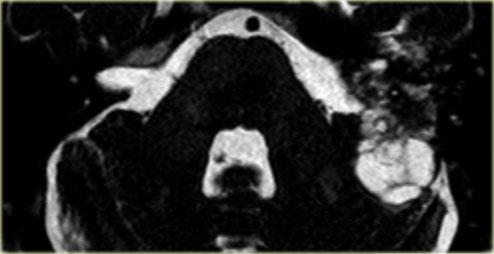

Nam giới 75 tuổi với cholesteatoma tái phát đã biết. Hình ảnh cho thấy khối có tín hiệu hỗn hợp trên chuỗi xung T1W mặt phẳng sagittal và tăng tín hiệu trên chuỗi xung T2W mặt phẳng axial. Khối tăng tín hiệu trên hình ảnh khuếch tán, cho thấy hạn chế khuếch tán. (các mũi tên)

Cholesteatoma có tín hiệu hỗn hợp trên chuỗi xung T1W và tăng tín hiệu trên chuỗi xung T2W.

MRI đặc biệt hữu ích trong việc đánh giá mức độ lan rộng của cholesteatoma vào hố sọ giữa và/hoặc hố sọ sau, cũng như phát hiện khả năng thoát vị của các cấu trúc nội sọ vào xương thái dương – đặc biệt sau phẫu thuật.

Sau khi tiêm thuốc tương phản từ tĩnh mạch, MRI có thể phân biệt mô hạt với tràn dịch.

MRI khuếch tán có thể phân biệt cholesteatoma – vốn có hạn chế khuếch tán – với các bất thường khác, đặc biệt là mô hạt – vốn có đặc điểm khuếch tán bình thường (hình minh họa).